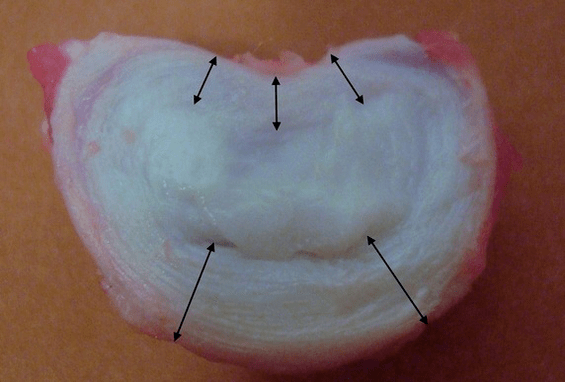

Her bir intervertebral disk iki farklı bölümden oluşur:

- diski çevre çevresinde dışarıdan kaplayan yoğun liflerden oluşan dış lifli halka;

- iç elastik bileşen nükleus pulposustur.

Annulus fibrozusun lifleri çok yoğun ve elastiktir. Yıllar geçtikçe elastikiyet kaybolur ve 60 yaşına gelindiğinde lifli halka sertleşir. Üstteki ve alttaki omurların yüzeyi ile diskin kendisi arasında uç plakalar, yani omur ile disk arasındaki sınır bölgeleri bulunur. Bu uç plakalar nedeniyle omurların yüksekliği artar ve bunlar aracılığıyla, diskin kıkırdağı kanla beslenmediğinden veya innerve edilmediğinden, çekirdek pulposus ve intervertebral diskin dokuları difüzyon yöntemiyle yaygın olarak beslenir.

Genç bir insandaki sağlıklı intervertebral diskler yüksek metabolizma hızlarına sahiptir. Kontrastı normal bir diske eklerseniz, 20 dakika sonra kaybolur.

Yani bel bölgesinde, en büyük yük nedeniyle disklerin kalınlığı en fazladır. Laboratuvar çalışmaları, genç bir insandaki tek bir sağlıklı diskin 2,5 tona kadar statik basınç yüküne dayanabildiğini göstermiştir. 70 yaşında bu rakam 110 kg'a düşüyor! Yani, "eski ve kurumuş bir disk", yükü yanlara aktarmak ve halka içinde artan basıncı korumakla 22 kat daha kötü başa çıkıyor.

Bu neden oldu? Zamanla lifli halka yavaş yavaş aşınır. Artık esneyemez, yalnızca diskin dışına doğru çıkıntı yapar veya kırılır. Çekirdek, dikey yükün iletilmesini ve radyal yüke dönüştürülmesini durdurur. Yaşla birlikte stres yavaş yavaş disklerin içinde birikir ve yapıları değişir. Ayrı bir diskte alınan tüm bu işlemler omurganın tamamına aktarılırsa klinikte osteokondroz denilen bir durumla karşı karşıya kalırız. Artık tanımlamaya başlayabiliriz.